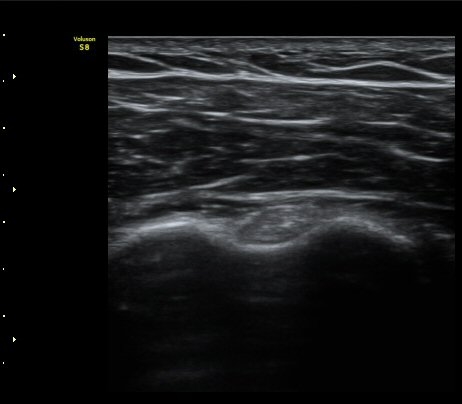

ÀÌµÎ¹Ú±Ù°Ç È¾´Ü¸é°Ë»ç¿¡¼­ ƯÀÌ ¼Ò°ß ¾øÀ½

(no specific abnormal findngs with transverse scan of biceps tendon) »çÁø 1, 2